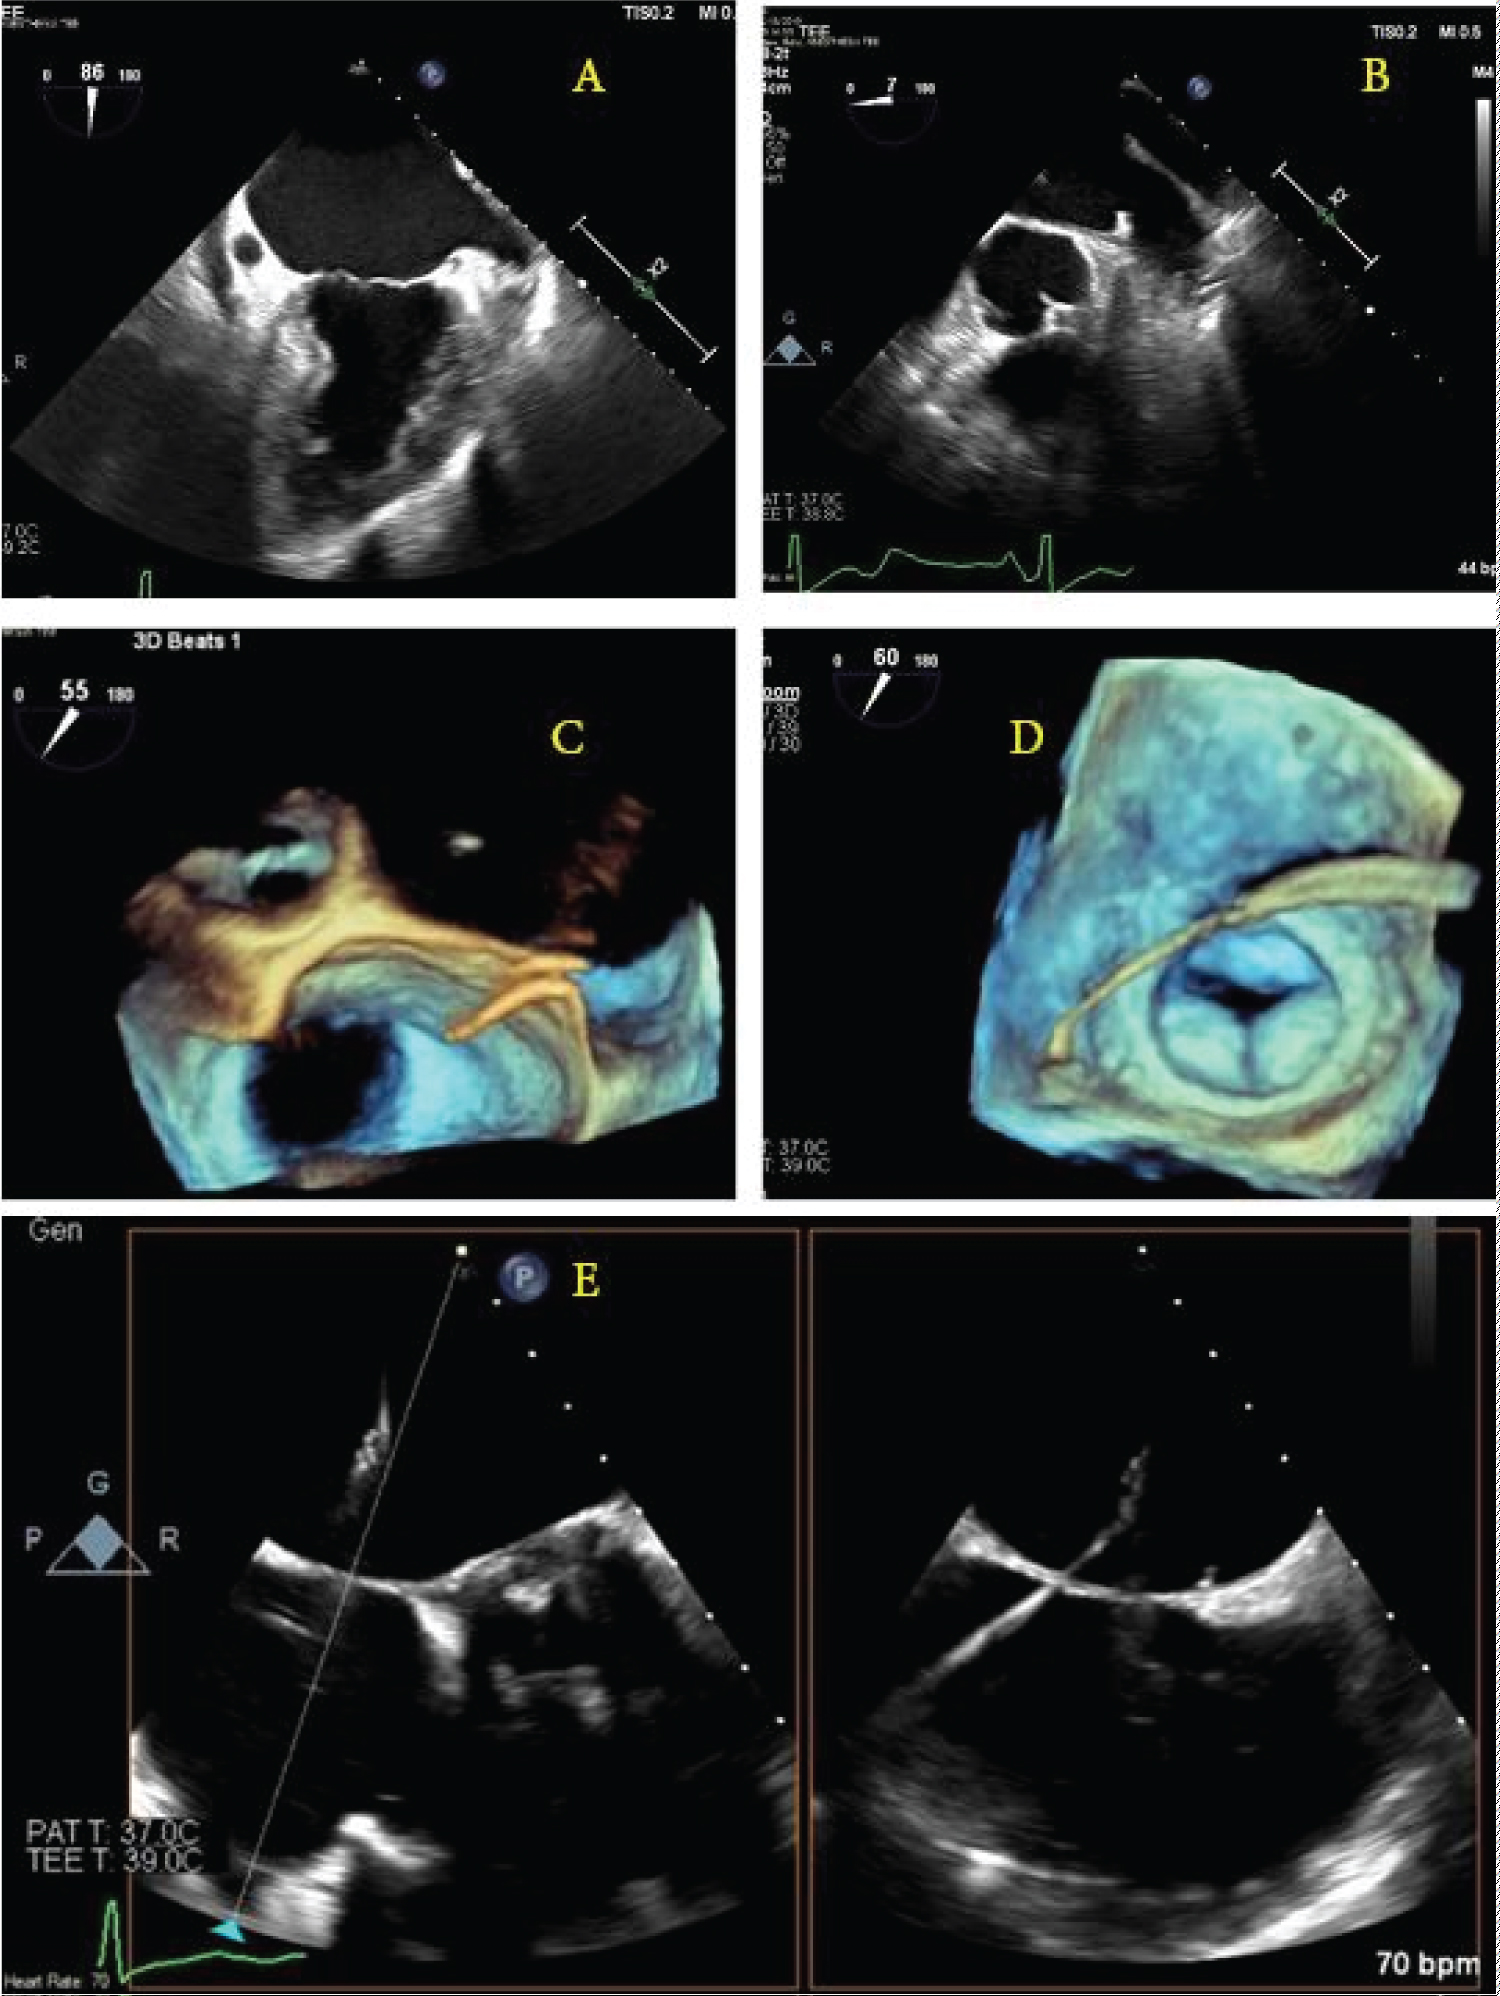

A chest X-ray may show a widened mediastinum or pneumomediastinum; if oral contrast is used as in a fluoroscopic swallow study, a leak may be seen during the imaging series. Computed tomography scanning with intravenous and oral contrast is the best imaging study at this point and is usually only positive late in the course of the disease, with findings including pneumomediastinum or pneumopericardium (Figure 2) [34]. The morbidity and mortality of open surgical operations for repair are high, but compared to conservative medical therapy or endoscopic stenting, early surgical intervention provides the best chances of survival [35], as earlier studies have shown almost 100% mortality by endoscopic stenting of the perforation [36]. Options for surgical repair include: 1) Median sternotomy with full use of cardiopulmonary bypass, patch repair of atrial defect from within the left atrium, followed by endoscopic stenting of the esophagus; 2) Right thoracotomy with femoral-femoral bypass, patch repair of atrial defect from either within or external to the left atrium, followed by placement of a pedicled muscle flap between the esophagus and atrium [37]; and 3) Median sternotomy with full use of cardiopulmonary bypass, patch repair of the atrial defect from within the left atrium, followed by left thoracotomy for positioning of the muscle flap between the esophagus and left atrium.

Figure 2: Radiographic findings of AEF. (a) Widened mediastinum on chest X-ray; (b) Computed tomography showing pneumopericardium with air tracking up the ascending aorta.